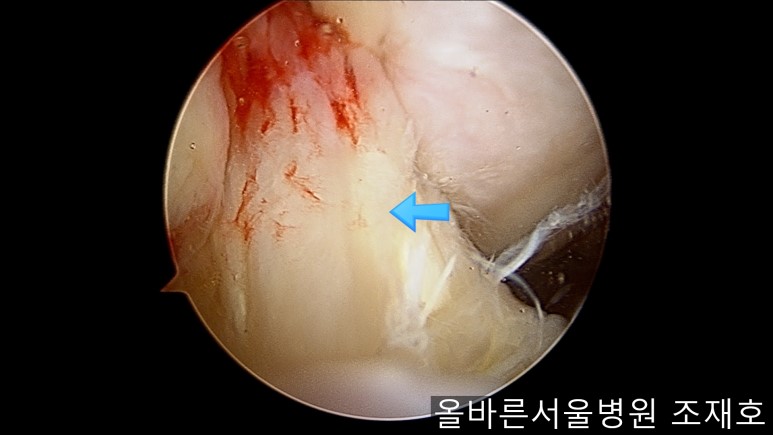

在股骨部位用CARTISTEM注射用4mm激光钻细密打孔,并确保软骨板不倒塌。不用切开通过关节镜即可完成手术。

如图,尽量细密打孔。

用水冲洗清理空间,为注入CARTISTEM做准备。

以注射的方式将CARTISTEM填满每一个孔。

填充完每个孔后将剩余的CARTISTEM涂抹在孔上方。